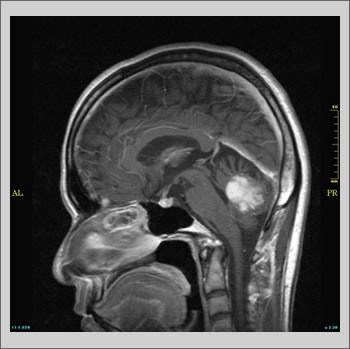

36歳女性、小脳腫瘍(星細胞腫)

MRIではあらゆる方向から病変部を容易に観察できます。この症例では頭部を3つの方向から観察しています。